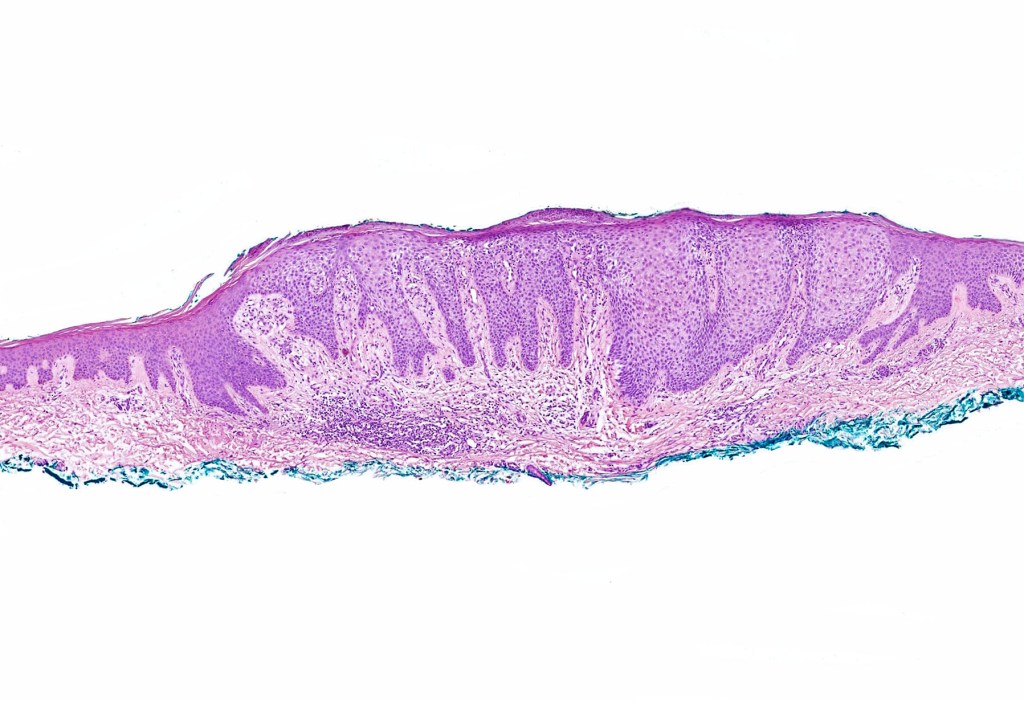

•Sharply demarcated acanthosis/psoriasiform hyperplasia; bland epithelium

•Fusion of rete ridges

•Vascular dilatation in the dermal papillae and a perivascular sometimes neutrophil-rich infiltrate